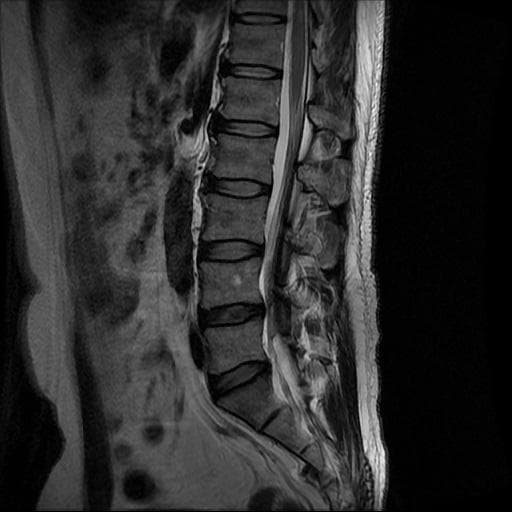

허리 MRI 디스크 상태 분석 부탁드립니다

검진 차 MRI찍었는데 분석 부탁드립니다.

건협에서는 관리해야 된다는데 디스크 협착이나 팽윤 등이 있는 상태인지 궁금합니다.

우선 현재로썬 사진만으론 판단을 하기에 제한이 되지만 사진상 디스크 상태는 심해보이지 않습니다.

요추부위의 하부 에서 약간의 팽윤이나 돌출로 의심해볼수 있는 정도이지만, 정확한 상태는 관련 전문의에게 진료시 문의를 하시는 것을 추천드립니다.